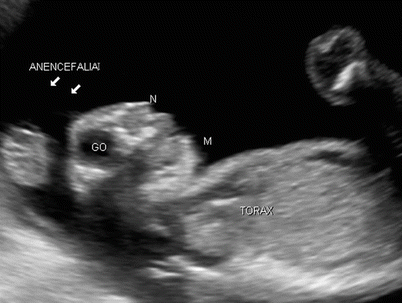

Fig. 4.10

Sagittal image of the fetal cephalic pole revealing the absence of the coating of the skullcap (arrows) with protruding eye globes (GO), a typical aspect observed in anencephaly cases

Fig. 4.12

Sagittal section showing the abrupt termination of bone structures in the fetal head and no brain parenchyma (anencephaly, arrows) in an anencephalic fetus. J = fetal knee, TO = thorax, N = nostrils, M = chin